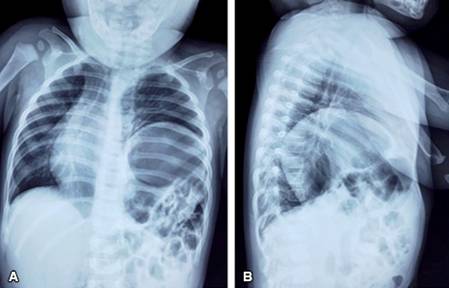

Inició su padecimiento aproximadamente cuatro horas previas a su ingreso presentando de manera súbita tos seca, posteriormente flemosa, dificultad para respirar, vómito y cianosis; 15 minutos más tarde presenta nuevamente misma sintomatología por lo que acude al Servicio de Urgencias. Durante su valoración en urgencias se encontró en la exploración física tórax normolineo con movimientos de amplexión y amplexación normales, auscultación pulmonar con presencia de ruidos peristálticos en región basal de hemitórax izquierdo, resto de campos pulmonares con ruidos respiratorios normales, el abdomen estaba en batea (Figura 1), blando, depresible, con ruidos peristálticos disminuidos en intensidad y frecuencia, sin datos de irritación peritoneal ni visceromegalias. Se realizó radiografía toracoabdominal anteroposterior y lateral de tórax (Figura 2) donde se encuentran múltiples imágenes radiolúcidas de bordes bien delimitados, así como elevación del hemidiafragma izquierdo hasta quinto espacio intercostal izquierdo, desplazamiento del mediastino hacia el hemitórax derecho y ausencia de cámara gástrica y asas intestinales en abdomen.

Figura 2: Radiografías de tórax al ingreso. Panel A: proyección anteroposterior. Panel B: proyección lateral izquierda. Se observa elevación del hemidiafragma izquierdo hasta quinto espacio intercostal y desplazamiento del área mediastinal hacia hemitórax derecho.